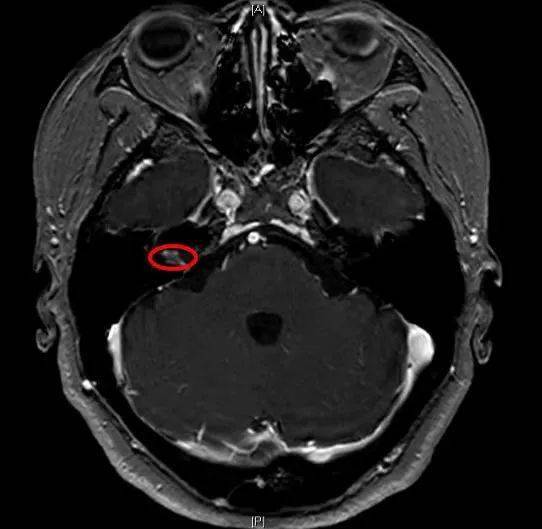

图为核磁影像下内听道肿瘤

患者王女士的经历则更为“惊险”。最近一年多,患者右耳的听力逐渐下降至听力基本丧失,她以为是年纪大了就没有在意。但是最近两三个月又多了头晕的毛病,走路像踩棉花不稳当,好几次还差点摔倒。伊海金医师为患者安排了内听道磁共振检查,发现其右侧内听道长了一个肿瘤。内听道是一根狭窄的骨管,里面容纳着多根神经,如果肿瘤继续生长,不但会导致听力下降、眩晕及平衡功能障碍,还有可能导致面瘫。在叶京英主任支持下,伊海金联合神经外科主任郭毅,带领许嘉、高娟娟医师为患者进行微创经迷路听神经瘤切除术,拆掉了耳朵里面的“危险分子”,还保留了面神经功能,避免了传统开颅手术的巨大风险。